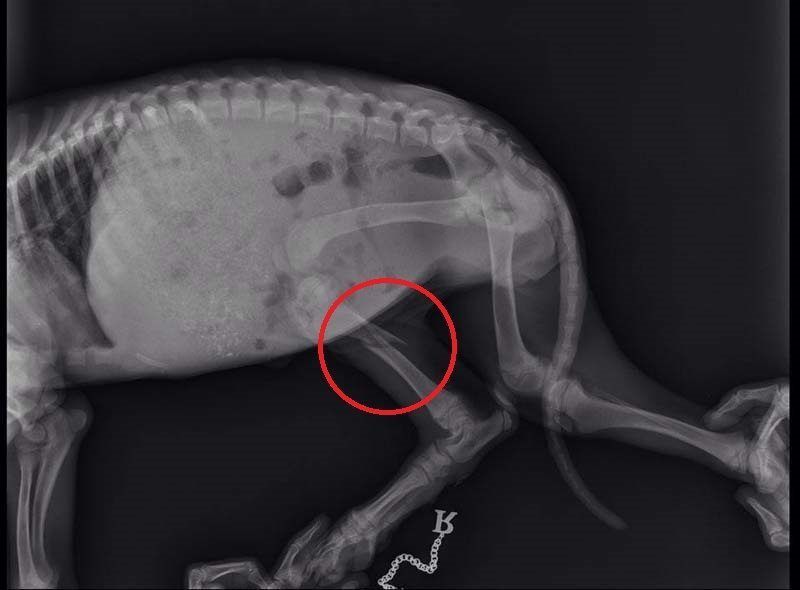

Το κουταβάκι που βλέπετε στις φωτογραφίες εντοπίστηκε χθες στο Άκτιο να κλαίει από τους πόνους κοντά στα διόδια της υποθαλάσσιας σήραγγας καθώς όπως αποδείχτηκε έχει σπασμένα τα δύο πόδια του ενώ είναι χτυπημένο και στην κοιλιά. Το πως τραυματίστηκε το ζώο παραμένει άγνωστο αν και σύμφωνα με τον κτηνίατρο Νίκο Ρώσσο, που το εξέτασε, κάποιος είναι πολύ πιθανό να το το κλώτσησε.

Η Δώρα Τσάτση μέλος του σωματείου «Παρέμβαση για τα Ζώα - Πρέβεζα» εξήγησε στο www.zoosos.gr ότι ο κ. Ρώσσος τους είπε πως είναι απίθανο το κουταβάκι, που ζυγίζει μόλις τέσσερα κιλά, να χτυπήθηκε από όχημα καθώς δεν έχει σημάδια και αυτά τα τραύματα προκαλούνται μόνο από κλωτσιά.

Εξαιτίας του νεαρού της ηλικίας του κουταβιού δεν θα γίνουν όλες οι επεμβάσεις ταυτόχρονα. Αρχικά θα χειρουργηθεί στην κοιλιά και στην συνέχεια θα ακολουθήσουν οι επεμβάσεις στο πίσω πόδι του που έχει σπάσει σε δύο σημεία και στη συνέχεια στο μπροστινό.